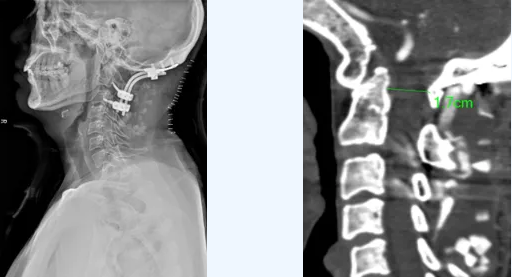

近日,郑州大学第五附属医院骨科二病区成功开展一例高难度的后入路寰枢椎复位钉棒内固定术,顺利解除了患者高位颈髓的严重压迫。

三维手术规划:利用CT血管成像进行三维重建,精确描绘椎动脉异常走行路径,为每一颗螺钉规划出安全的“植入通道”。

2.实施后路复位固定术(核心步骤)

在神经电生理监测与术中全程透视的“双重护航”下,手术团队凭借丰富经验,于解剖结构复杂的“危险区域”精准操作,成功置入全部螺钉,未损伤椎动脉。随后利用钉棒系统,安全、有效地对脱位的寰枢椎进行复位,并植入人工骨实现永久性稳定融合。